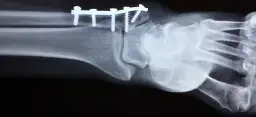

Czy RTG jest zawsze konieczne? Rola prześwietlenia w wykluczaniu złamań

Tak, zdjęcie rentgenowskie (RTG) jest niemal zawsze konieczne po urazie stawu skokowego, zwłaszcza jeśli występują objawy alarmowe lub trudności w obciążaniu nogi. Jego głównym celem jest wykluczenie złamania kości. Skręcenie i złamanie mogą dawać podobne objawy, dlatego precyzyjna diagnostyka jest niezbędna, aby dobrać odpowiednie leczenie. Wykluczenie złamania daje pewność, że możemy skupić się na leczeniu tkanek miękkich.USG stawu skokowego: Co pokaże badanie i dlaczego jest tak ważne?

Po wykluczeniu złamania często wykonuje się badanie ultrasonograficzne (USG) stawu skokowego. USG jest niezwykle ważne, ponieważ pozwala ocenić stan tkanek miękkich przede wszystkim więzadeł, które są najczęściej uszkadzane podczas skręcenia. Dzięki USG lekarz może określić stopień uszkodzenia więzadeł (naciągnięcie, częściowe zerwanie, całkowite zerwanie), obecność płynu w stawie czy krwiaków. Ta informacja jest kluczowa dla zaplanowania dalszego leczenia i rehabilitacji.